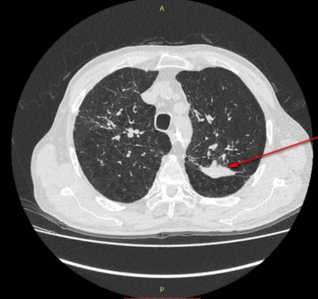

Милиарный туберкулез на КТ характеризуется множественными мелкими очагами (несколько миллиметров в поперечнике) во всех отделах легких . Очаги появляются и в других органах, т .к . инфекция . . .

Туберкулез на КТ: легких, виден ли, что показывает, как выглядит, описание, картина . Выявление туберкулеза на начальных этапах развития — одна из главных задач медицины .

Туберкулез на КТ легких можно определить с большой долей вероятности . Томографию считают более чувствительным способом диагностики, чем рентген . Однако на основании результатов только компьютерного сканирования . . .